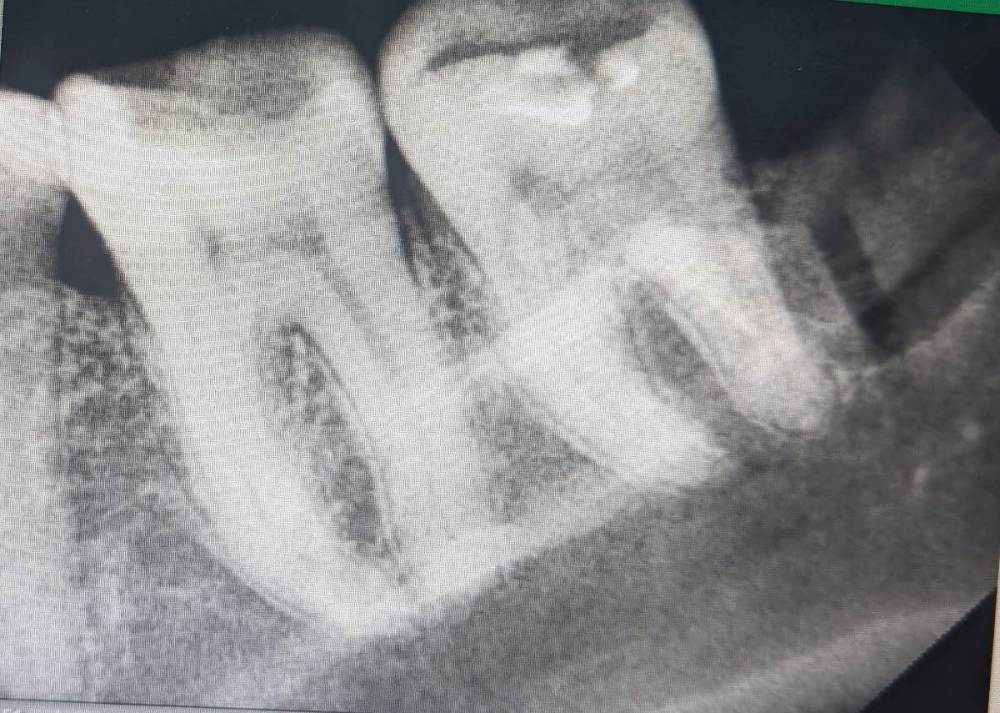

Govanna Опубликовано 23 января, 2024 Автор Поделиться Опубликовано 23 января, 2024 Врач который удалил в платной клинике, сказал все в порядке, пошла к другому- говорит гной, завтра заканчиваю пить антибиотики, а отек все ещё сильный. Посмотрите, пожалуйста, на снимке все в порядке? Действительно ли правильно так выпиливать? Ссылка на комментарий

Женька Опубликовано 23 января, 2024 Поделиться Опубликовано 23 января, 2024 @Govanna по этому снимку видно, что коронковая часть зуба точно отсутствует, не более того. 1 Ссылка на комментарий